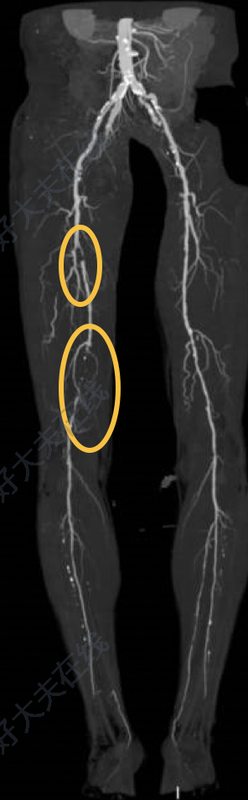

治療前男性69歲,右下肢行走困難5年,加重到慢走100米需要休息有1年多時間,合并糖尿病、冠心病、抽煙的情況。檢查右下肢股淺動脈兩處病變,近端重度狹窄,遠端完全閉塞,位于圖中兩處橢圓形標記處。治療中術(shù)中采用多根導管和導絲配合開通股淺動脈成功后,開始采用小球囊擴張,擴開閉塞段,該病例鈣化不嚴重,血管彈性回縮不明顯,考慮可以不使用支架治療,交換置入遠端血管保護傘后,采用斑塊旋切術(shù),多個角度切除血管內(nèi)斑塊,圖3可見切除的部分斑塊,恢復血管通暢,為了減輕術(shù)后內(nèi)膜增生,采用藥涂球囊擴張原重度狹窄和閉塞段。治療后治療后30天該患者下肢動脈閉塞,鈣化不嚴重,采用斑塊旋切加藥涂球囊治療,避免植入支架,效果良好。此類患者一般是全身多處動脈硬化,如果沒到手術(shù)治療的程度,都給予藥物治療、加強鍛煉行走,動脈粥樣硬化性疾病容易復發(fā),所以必須加強到醫(yī)院就診和隨訪,此患者需要戒煙也是很關(guān)鍵的治療部分。